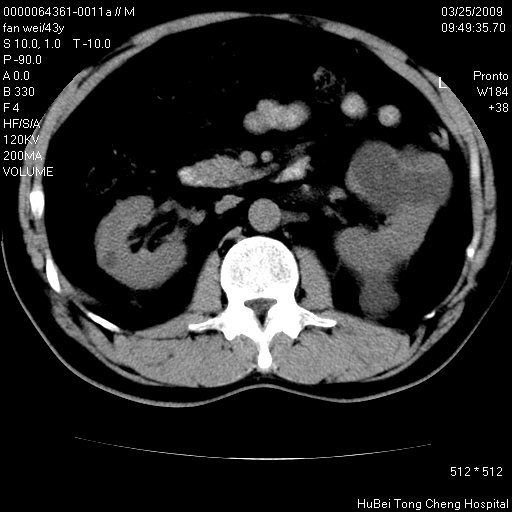

双肾ct轴位平扫+增强扫描(层厚10mm,螺距1.0,重建间隔10mm),图像如下:

多囊肾的影像诊断标准:有阳性家族史,年龄<30岁,单侧或双侧肾脏有两个肾囊肿;30~59岁,两侧肾脏各有两个肾囊肿;60岁以上,每侧肾脏有4个囊肿。敏感性和特异性达86%和80%。

此病例影像诊断符合,要结合家族史,腰痛、血尿、尿路感染史,有无高血压等综合判断,如无相应的临床症状,本身病变也无意义了(个人观点)

左肾体积变大,支持多囊肾。

双侧多囊肾!

囊肿数得清,肾功能正常,考虑多发肾囊肿.另外,右肾后极突向肾周间隙的那个病灶是不是错构瘤,请楼主调窗看看.